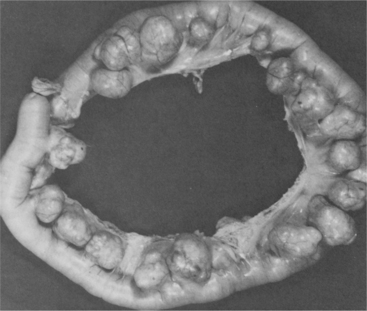

Diverticular disease is the term used to describe diverticulosis (uncomplicated disease) and diverticulitis (disease complicated by inflammation). Diverticulosis refers to the presence of outpouchings (diverticula) in the wall of the colon or small intestine, a condition in which the mucosa and submucosa herniate through the muscular layers of the colon to form outpouchings containing feces (Fig. 16-16).

Figure 16-16 Multiple diverticula in resected section of the colon. Weak spots in the muscle layers of the intestinal wall permit the mucosa to bulge outward (herniate) into the pelvic cavity. (From Rosai J: Ackerman’s surgical pathology, ed 7, St Louis, 1989, Mosby.)

When food particles or feces become trapped in the diverticula and the pockets become infected and inflamed, then diverticulitis can develop. This acquired deformity of the colon is rarely reversible and usually asymptomatic. The most common site is the sigmoid colon (95% of cases) because of the high pressures in this area required to move stool into the rectum, but any segment of the colon may be involved.